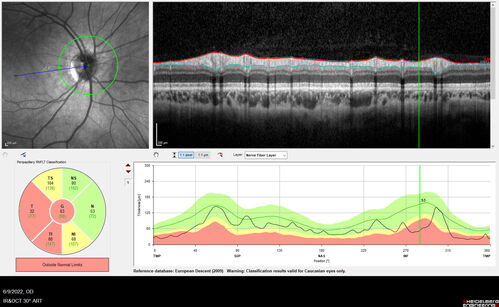

Autosomal Dominant Optic Atrophy - OPA1 Mutation

25 year old female with VA 20/80 OU and recent vision decline. Her father also has poor vision.